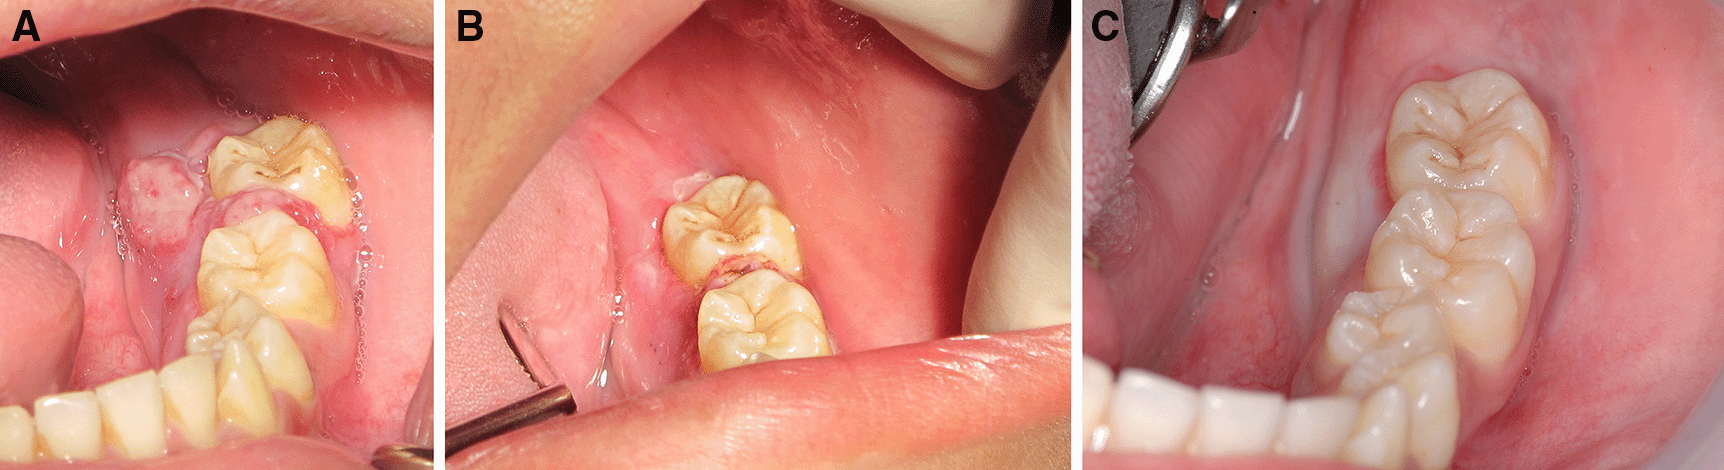

This case report was authorized by the ethics committee in human research, Khon Kaen University, reference number HE632040. The informed consent in Thai language from the patient and his parent was submitted to the ethics committee. The patient was a 13-year-old Thai male patient with a chief complaint of a rapidly swelling mass of the lower-left molar gingivae without pain for 10 days. There was no history of medical and psychological disorders of the patient and family. There was no systemic disease based on physical examination and laboratory investigation. The oral examination found an approximately 2×2 cm erythematous pedunculated mass with ulceration in the area of the interdental papilla and on the lingual gingiva of tooth no. 36 and tooth no. 37. The mass was soft consistency with no bleeding and no pus (Figure 1A). Tooth no. 37 exhibited buccal displacement, as shown in Figure 1B. Tooth no. 36 and tooth no. 37 exhibited second-degree and third-degree mobility, respectively.

A. The erythematous pedunculated mass at tooth no. 36 and tooth no. 37.

B. Tooth no. 37 was displaced from the normal position.

The patient was invited to have appointments for interstitial-intralesional laser therapy as previously described every two to three weeks. The remission of the pyogenic granuloma was observed, as shown in Figure 6A, B and C.

A. 2 weeks after the first therapy.

B. 2 weeks after the second therapy.

C. 3 weeks after the third therapy.